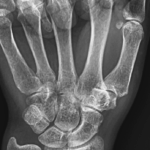

[doctormodu]2 CMC arthritis X ray

03 CMC joint arthritis